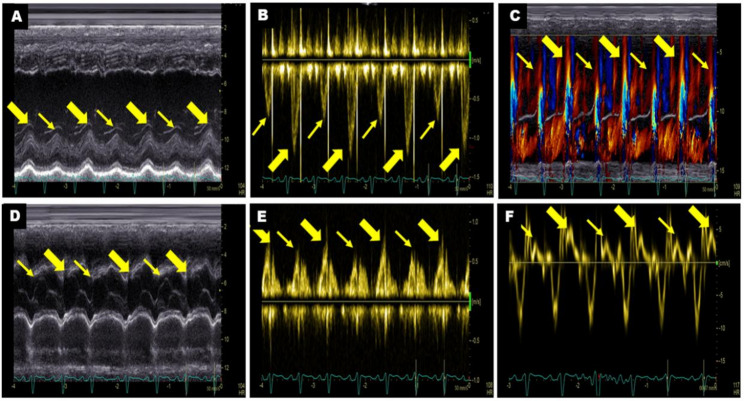

Background: Pulsus alternans (PA) is an intriguing phenomenon and a clinically rare entity. Accurately assessing cardiac function in patients with PA remains challenging. This study aims to investigate the myocardial mechanical characteristics and non-invasive hemodynamic profiles of PA patients using multiple echocardiographic imaging modalities.

Methods: Clinical and echocardiographic data were retrospectively analysed from 16 patients diagnosed with PA by echocardiography at our hospital between January 2021 and May 2025. In this study, the characteristics of PA were elaborated by multiple echocardiographic methods, and the non-invasive hemodynamic profile was determined by pulse-wave Doppler.

Results: Sixteen patients were enrolled. Seven were classified as NYHA class III and six as class IV. Elevated levels of NT-proBNP and hs-cTNT were observed in most patients. Follow-up ranged from 1 to 44 months, and five patients experienced adverse outcomes, including heart transplantation, rehospitalisation, and death. Within this cohort, three patients exhibited biventricular PA, while 13 patients presented with left ventricular (LV) PA. Key hemodynamic parameters varied significantly: LVOT-VTIstrong beat ranged from 11.3 cm to 29.2 cm, LVOT-VTIweak beat from 6.8 cm to 22.1 cm, and the variation rate between strong and weak beats (∆LVOT-VTI) ranged from 19 to 52%. Global longitudinal strain (GLS) was significantly reduced in 14 patients (range: - 1.2% to - 10.4%), while peak strain dispersion (PSD) increased (range: 47 ms to 117.5 ms). Two patients were excluded from strain analysis due to suboptimal imaging. Hemodynamic parameters (LVOT-VTIstrong beat, LVOT-VTIweak beat and ∆LVOT-VTI) showed strong correlations with GLS in PA patients (r = 0.806, P = 0.001; r = 0.642, P = 0.018 and r = 0.611, P = 0.027, respectively). NT-proBNP was significantly positively related to adverse outcomes in PA patients (r = 0.669, P = 0.012).

Conclusion: Echocardiography is essential for evaluating cardiac function in patients with PA. This study used multiple echocardiographic methods to delineate the characteristics of this intriguing clinical phenomenon. Non-invasive hemodynamic parameters are potentially important for prognosis assessment, and myocardial strain assessment provides valuable insights into myocardial mechanical features. A comprehensive analysis using multimodality imaging is crucial for accurately identifying this disease, potentially enhancing the understanding of the pathophysiological mechanism of PA.